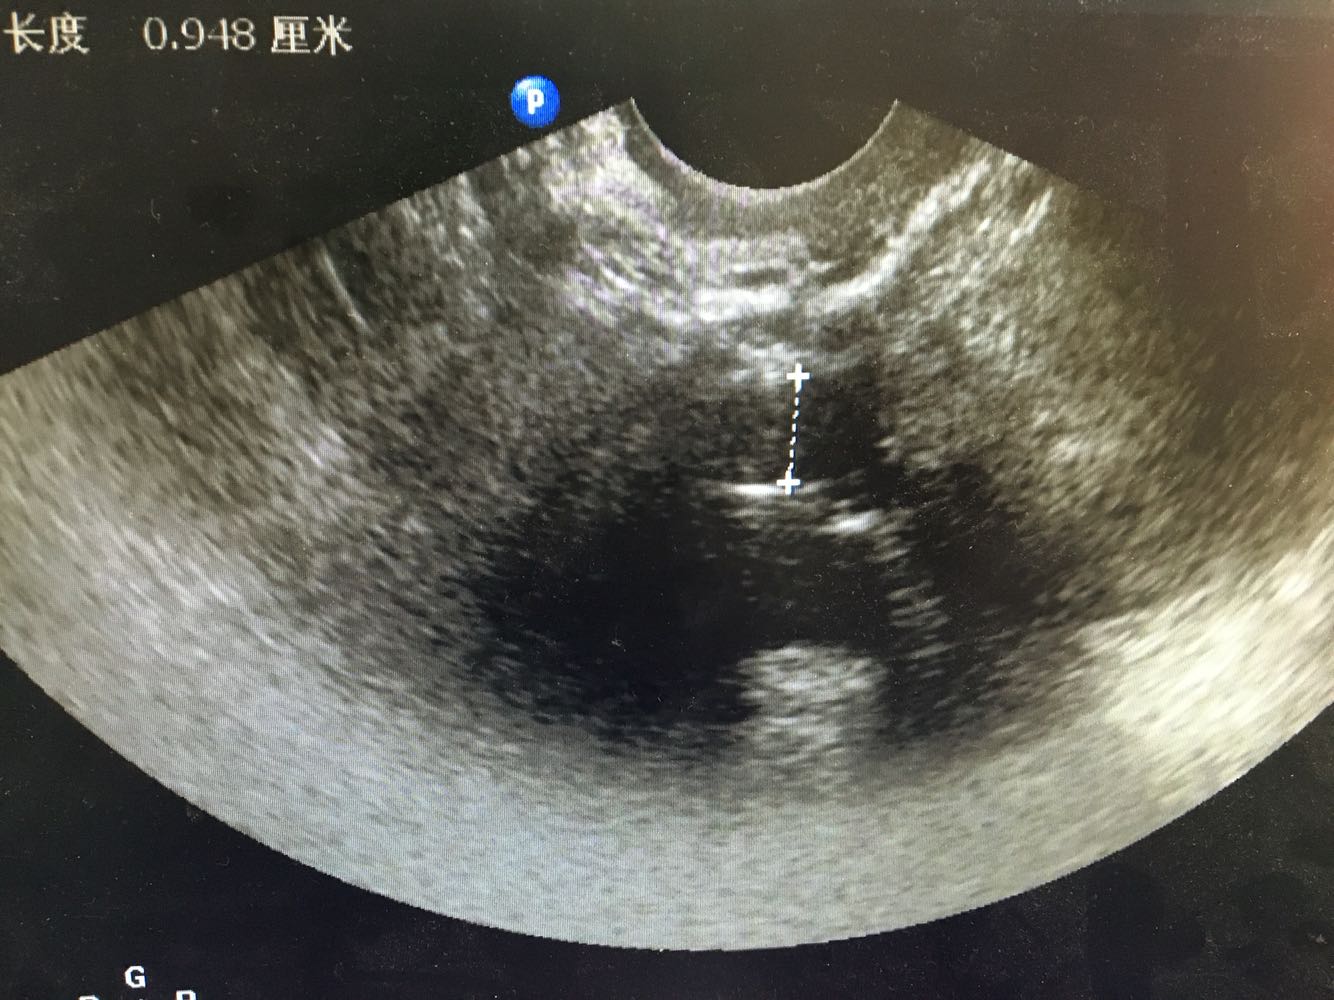

妇科检查:  妇科检查: 外阴(-);阴道畅,少量血性分泌物;宫颈轻糜,无活动性出血;宫体中位,常大,质中,无压痛;附件未及异常,无压痛。 辅助检查:我院 【ECG】ST段改变。    【妇科B超】内膜双侧厚:16,回声不均匀,内引出血流信号,与周围肌层分界不清。诊断意见:子宫内膜增厚,回声不均匀,Ca待查,请结合临床。

诊断:绝经后出血 诊疗方案:患者入院后完善各项检查排除手术禁忌症,行B超下分段诊刮术,刮勺搔刮宫颈管极少量组织刮出,并涂片送检脱落细胞。 探宫腔深6.5cm,刮勺搔刮宫腔四周2圈,感宫壁滑腻,刮出少量鱼肉样组织,送病理, 同时涂片送检脱落细胞 ,手术顺利。